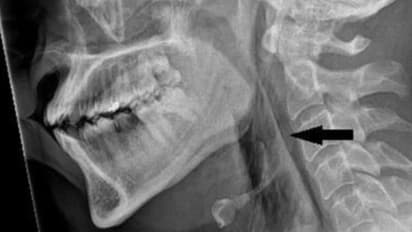

এই ঘটনার পর ওই ব্যক্তির গলার এক্স-রে করা হয়। সেখানেই আসল ঘটনা সামনে আসে। জানা যায় যে লোকটির অস্ত্রোপচারের এমফিসেমা ছিল, একটি রোগ যেখানে বাতাস ত্বকের গভীরতম টিস্যু স্তরের পিছনে আটকে যায়। পরবর্তীকালে, একটি সিটি স্ক্যানে দেখা যায় যে তার ঘাড়ের তৃতীয় এবং চতুর্থ কশেরুকার মধ্যে ছিদ্রটি অবস্থিত ছিল। তার ওপর তার ফুসফুস এবং তার বুকের মাঝখানে বাতাস জড়ো হয়েছিল। চিকিত্সকরা জানিয়েছেন যে "এই শারীরিক পরিস্থিতিতে নাক এবং মুখ বন্ধ করে হাঁচি আটকানোর ফলে শ্বাসনালীতে দ্রুত চাপ তৈরি হওয়ার কারণে" এই বড় শারীরিক ক্ষতি হয়েছিল।